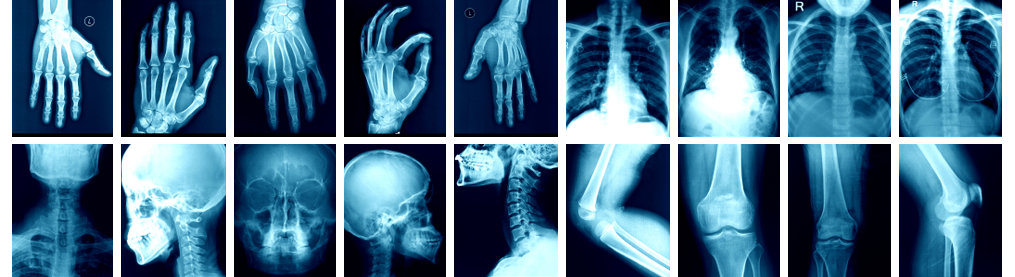

X-RAY services in Oxford

We are able to provide excellent radiographic (X-RAY | Oxford) images for the clinicians offering outpatient and inpatient care at St Luke’s Hospital.

We have particular expertise in the imaging of musculoskeletal disorders.